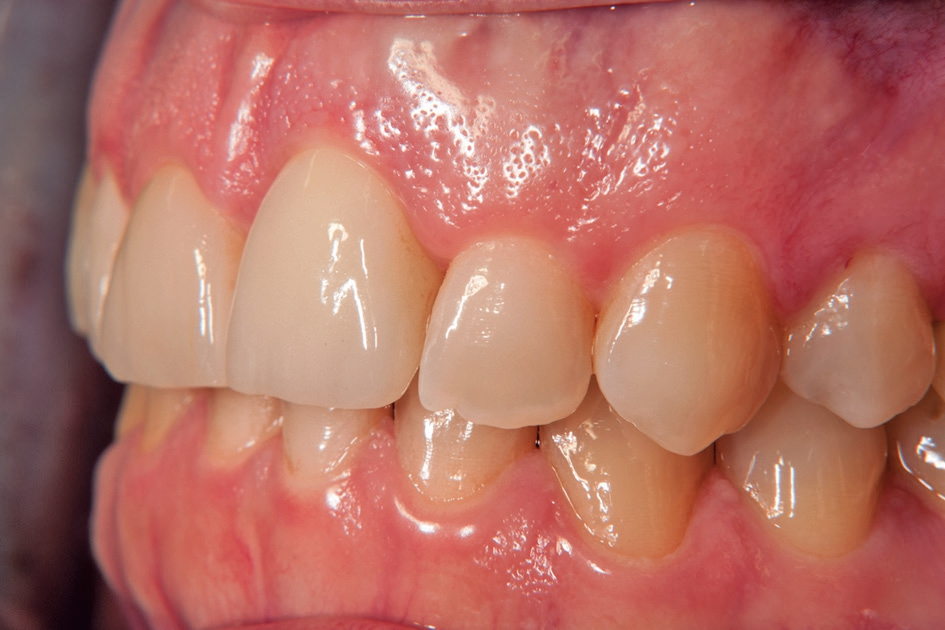

Gleichzeitig mit der prothetischen Versorgung des Implantats wurde auch für Zahn 11 ein Veneer geplant. Zum Einsatz kam ein Zeramex T Implantat Durchmesser 5,5 mm, Länge 12 mm. Für die Kronenversorgung wurde ein mit e. Max überpresstes CAD-Abutment gewählt. Während der Einheilphase des Implantats kam eine Sunflex-Prothese zum Einsatz.